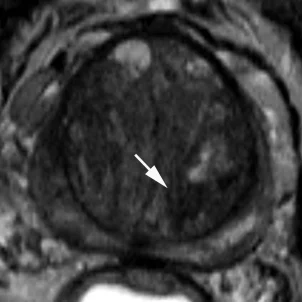

Transition Zone (TZ)

Неоднородная зона с нечеткими краями, все то, что не подходит в PIRADS 1-2 или 4-5

Вытянутой формы или не ограниченная гипоинтенсивная гомогенная зона, менее 1.5см

То же что и PIRADS 4, только размером более 1.5см или с распространением за пределы простаты